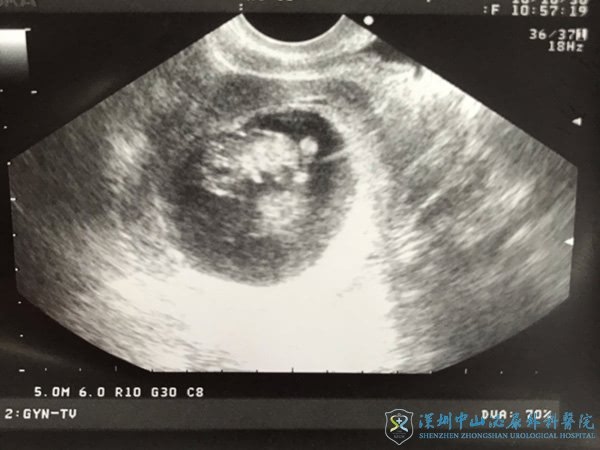

终于等到这一天我好紧张,因为认识的一位大姐,在我前几天开奖的,但是她一超没过,照不到胎心胎芽。等了一周后还是没照到,现在已经做了清宫手术。我上了b超台都还好紧张,听见护士说只看到一个孕囊,已经有胎心胎芽了,只是胎芽才5mm,刚刚合格。和我当天一起移植的有九个人中奖,9个人里有两个人怀双胞胎,我才成功了一个。其实我已经很满意了。放两个就是想妊娠率高一些。但是深圳中山泌尿医院不会让你第一次就移两个。医生把电脑转过来,让我看宝宝心跳,我看到一个小白点一闪一闪的,好激动!